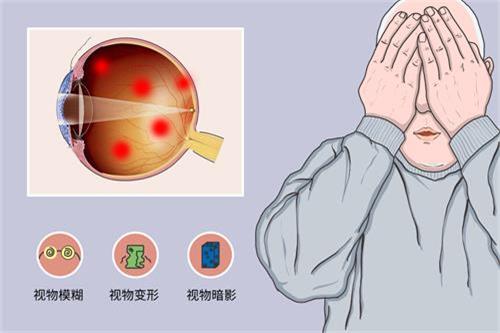

视网膜脱落治疗方法多样

视网膜脱落的治疗方法有多种。对于尚未发生脱离的视网膜裂孔,可采用激光治疗,利用激光封闭裂孔,防止视网膜脱落。传统的巩膜环扎术和巩膜外加压术,适用于单纯的早期视网膜脱离。

而对于病情复杂的视网膜脱落,如伴有玻璃体混浊、牵拉等情况,玻璃体切割视网膜复位联合手术是常用的治疗方式。

视网膜脱落手术并非小手术

视网膜脱落手术在眼科中属于较大的手术。常规的手术分为四级,视网膜脱落手术通常属于第四级。